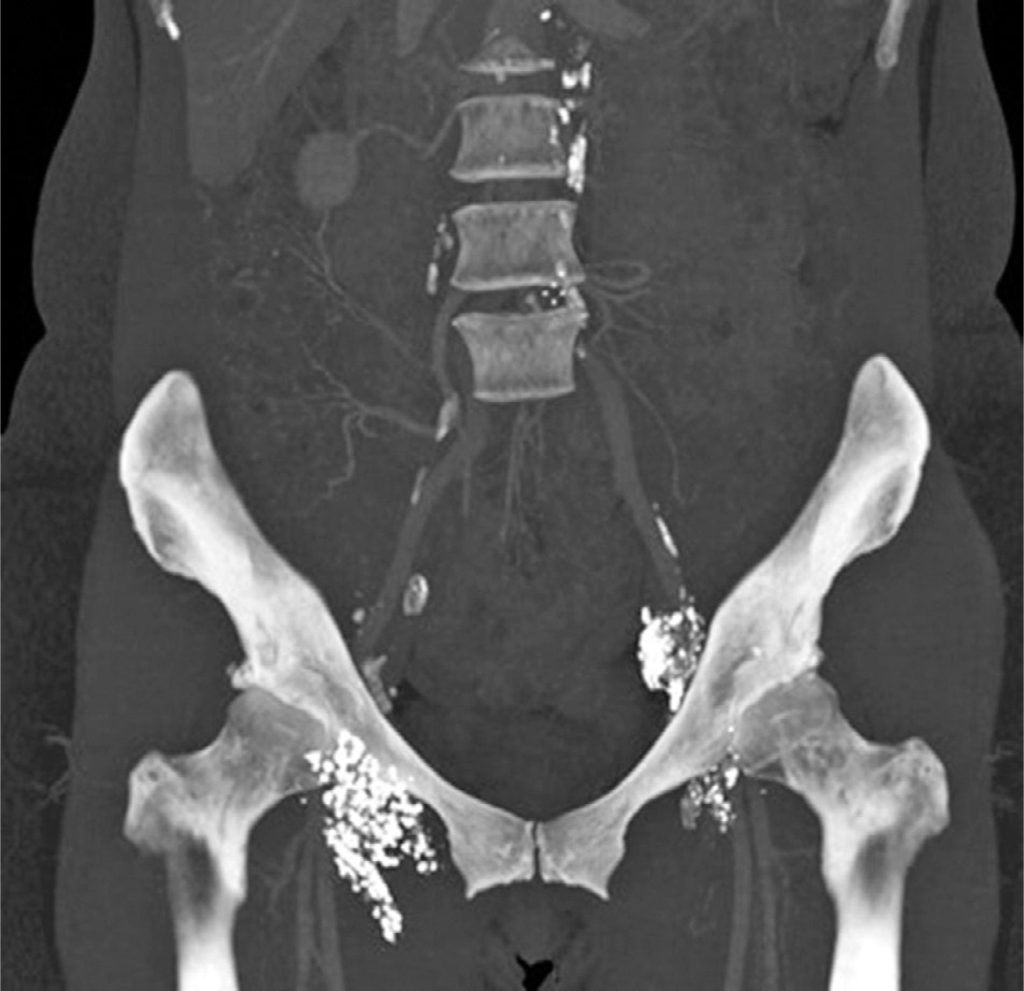

Percutaneous embolization of lymphatic leakage after pelvic lymphadenectomy

Lymphatic leakage after pelvic lymphadenectomy is a rare complication. Furthermore, in some cases, drainage is not possible or proves insufficient to resolve this complication. Therefore, more effective and minimally invasive interventional treatments are necessary. Accordingly, this case report presents a case of transafferent nodal embolization in a 50-year-old woman who underwent videolaparoscopic total hysterectomy with pelvic lymphadenectomy. The patient developed high post-surgery vaginal flow due to a lymphatic fistula, which was identified after intranodal lymphangiography and treated successfully via transafferent nodal embolization. This case report shows the importance of considering lymphatic leakage as a possible pelvic surgery complication, particularly when accompanied by local lymphadenectomy. Moreover, the case report reveals that intranodal lymphangiography and transafferent nodal embolization are safe and highly effective methods to detect and treat this complication. This prevents the need for follow-up surgery, which may add morbidity to an otherwise uneventful postoperative period.